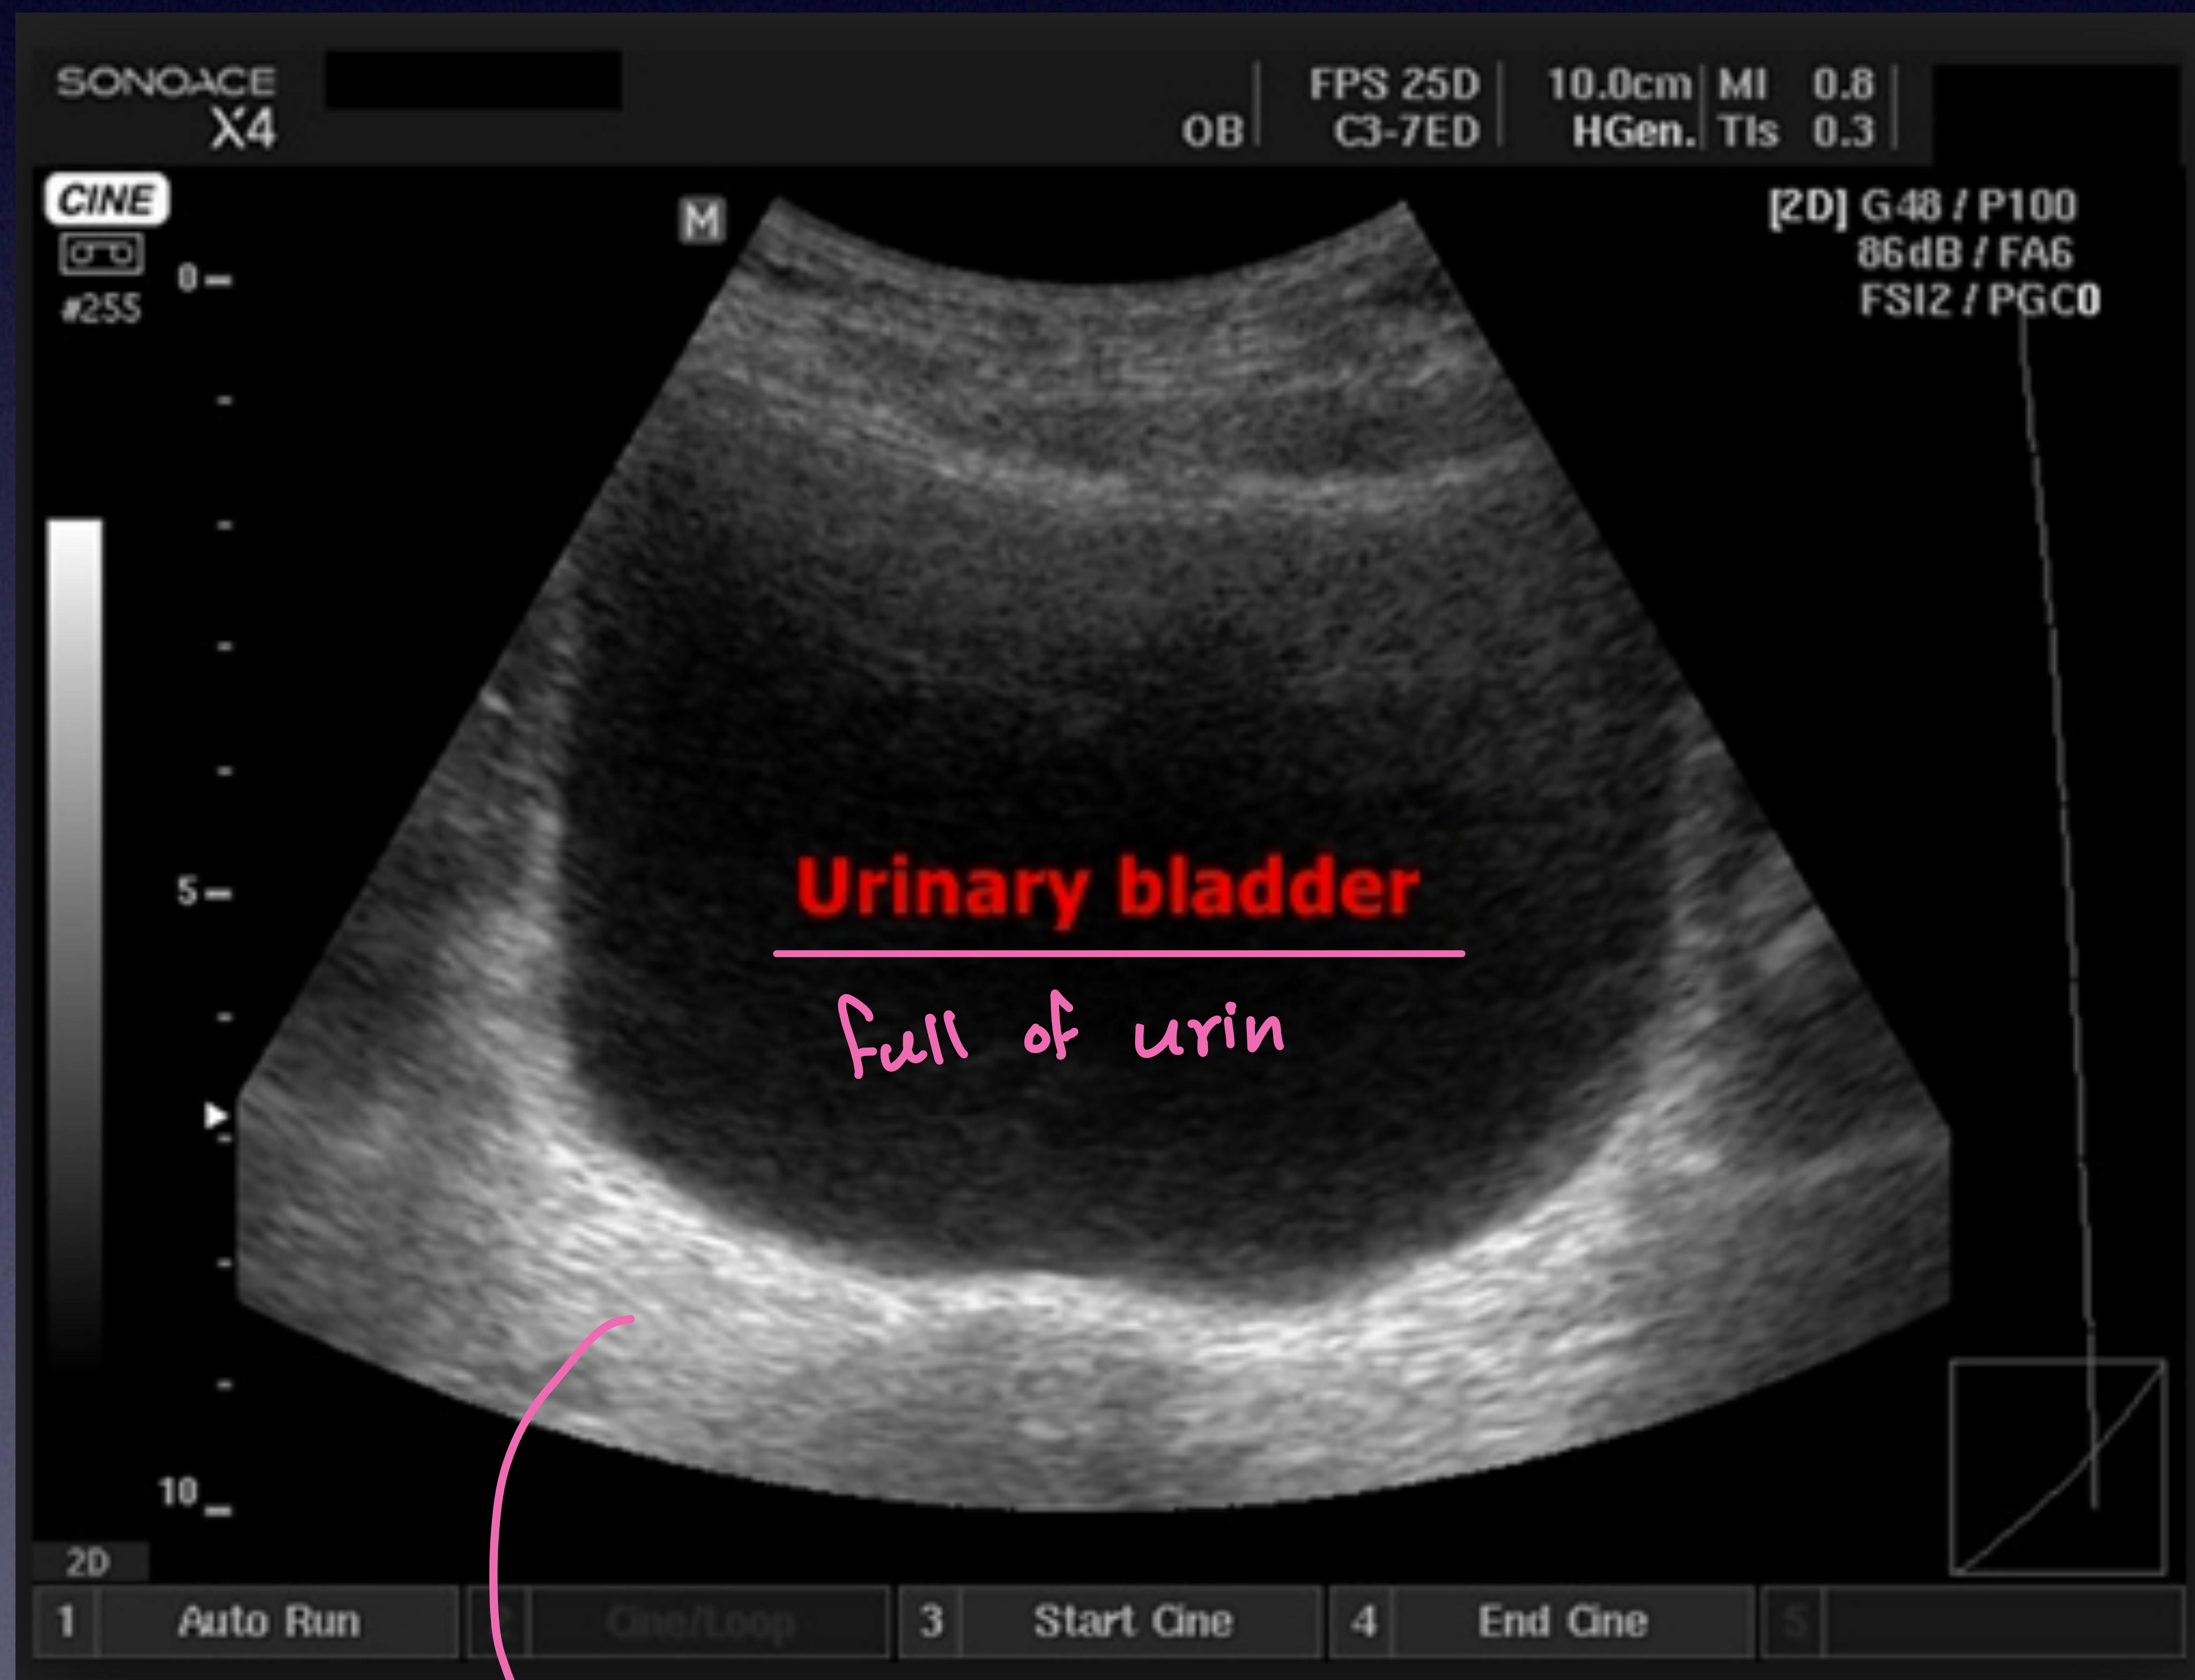

Bladder Scan (Suprapubic)

Midway between umbilicus and pubic bone.

Bladder full of urine (transverse view).

Blood in Douglas pouch (inferior to bladder).